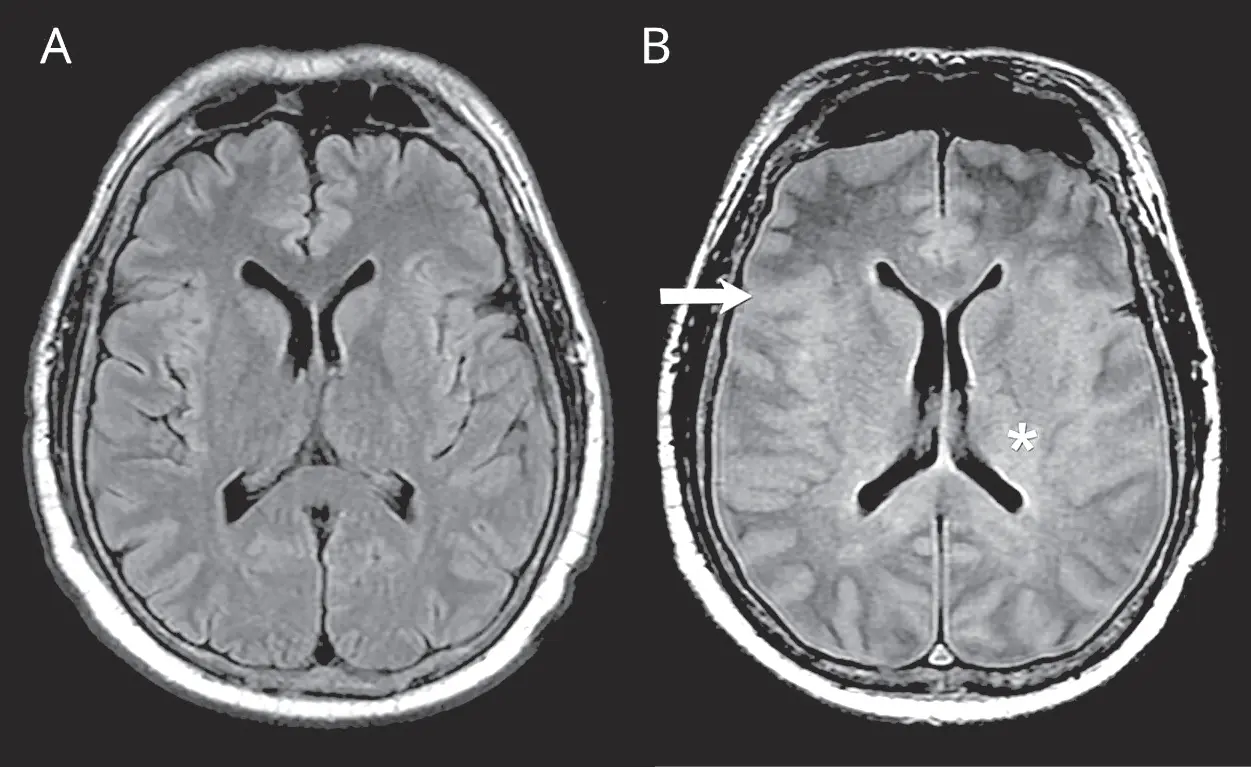

- Blutungen: Blutungen im Gehirn, zum Beispiel durch eine Hirnblutung, können zu einem Hirnödem führen.